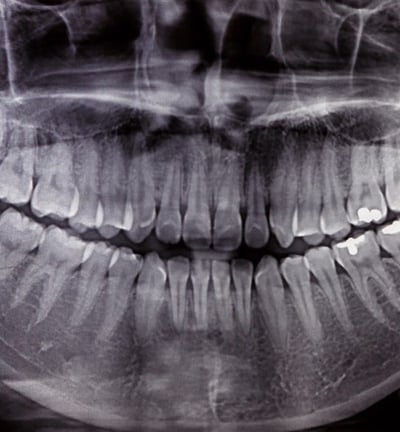

Radiographie panoramique :